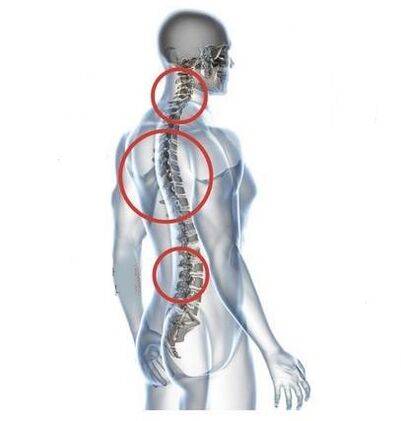

Symptoms of the disease

In the initial stage of development, osteochondrosis is asymptomatic.After a long stay with a bent head or intense physical activity, a mild discomfort occurs at the back of the neck.The patient is in no hurry to see a doctor, misunderstanding him about the consequences of muscle strain.The pathology progresses slowly but persistently.

Discomfort in the neck is gradually replaced by pain, dull pain in the neck, which intensifies after lifting weights, hypothermia or change of weather.Other specific symptoms of cervical osteochondrosis appear:

As the intervertebral discs and vertebrae become deformed, the patient's condition worsens.The course of osteochondrosis is complicated by neurogenic symptoms caused by compression by osteophytes or herniated protrusion of the spinal roots and vertebral artery.Headaches, dizziness, changes in blood pressure and reduced visual and auditory acuity appear.